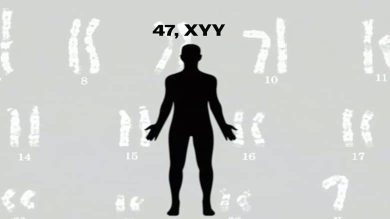

Jacob (47, XYY) Diğer Adıyla Süper Erkek Sendromu Nedir?

DNA’mız, bizi biz yapan şeydir. Nasıl göründüğümüz, vücudumuzun nasıl çalıştığı ve hatta kişiliğimiz bile onunla ilişkilidir. Her şey yolunda gittiğinde sistem…